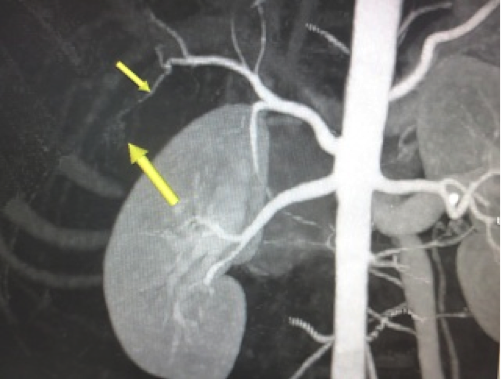

Tại Bệnh viện Từ Dũ, siêu âm và chụp CT tại Trung tâm Medic, phát hiện một thai sống khoảng 22 tuần trong ổ bụng vùng dưới hoành phải (dưới gan phải). Kích thước khối thai là 12x15x17cm. Bánh nhau dày 47mm, xâm lấn gan phải và có mạch máu nuôi xuất phát từ động mạch gan phải. Chẩn đoán: thai dưới gan, chỉ định mổ lấy khối thai và tiên lượng cuộc mổ khó nên mời phẫu thuật viên Bệnh viện Chợ Rẫy kết hợp cùng mổ.

![]() |

Hình 5. Thai nằm dưới gan (ngôi ngược) |

Hình 6. Thai trong ổ bụng. Thai ngôi ngược, có hình ảnh giống như thai trong tử cung nhưng không rõ hình tử cung, khối thai nằm dưới gan nên thấy đầu các xương sườn (Nguồn: ảnh phim Medic) |